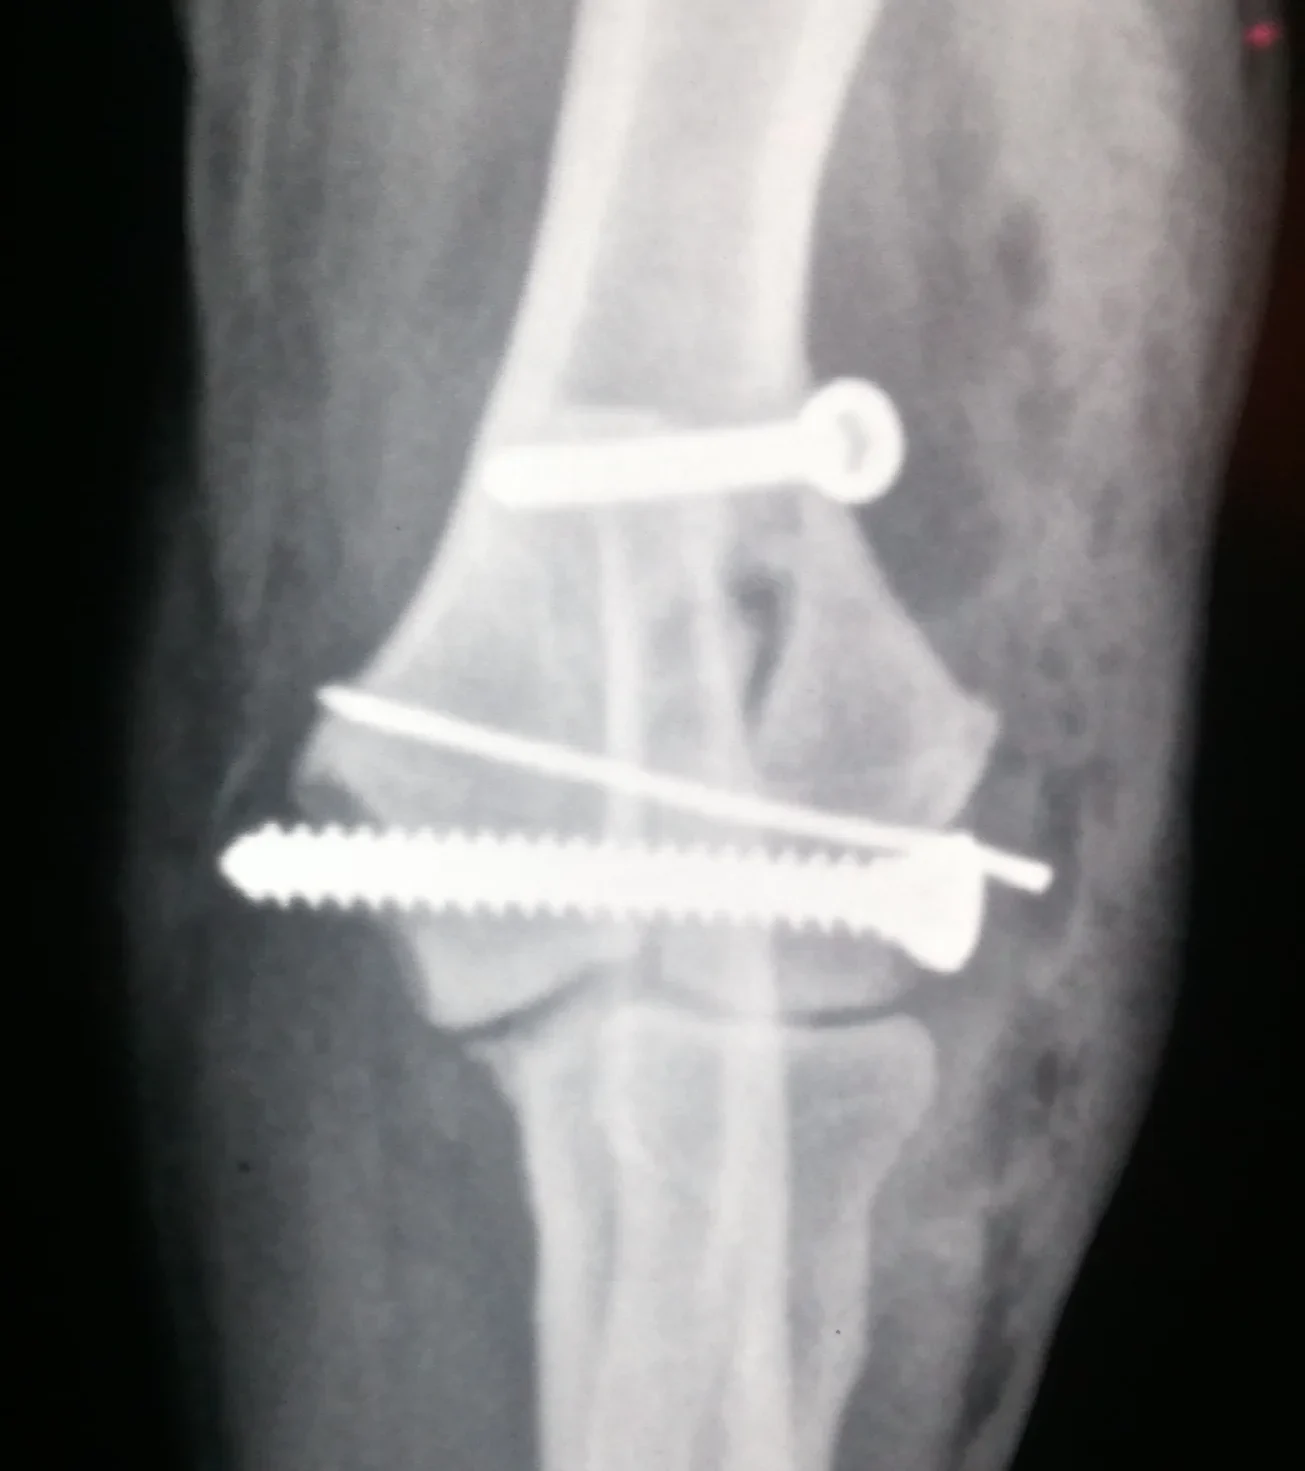

Galería de casos clínicos

Casos clínicos de cirugía (tejidos blandos, traumatología, neurocirugía, artroscopia)